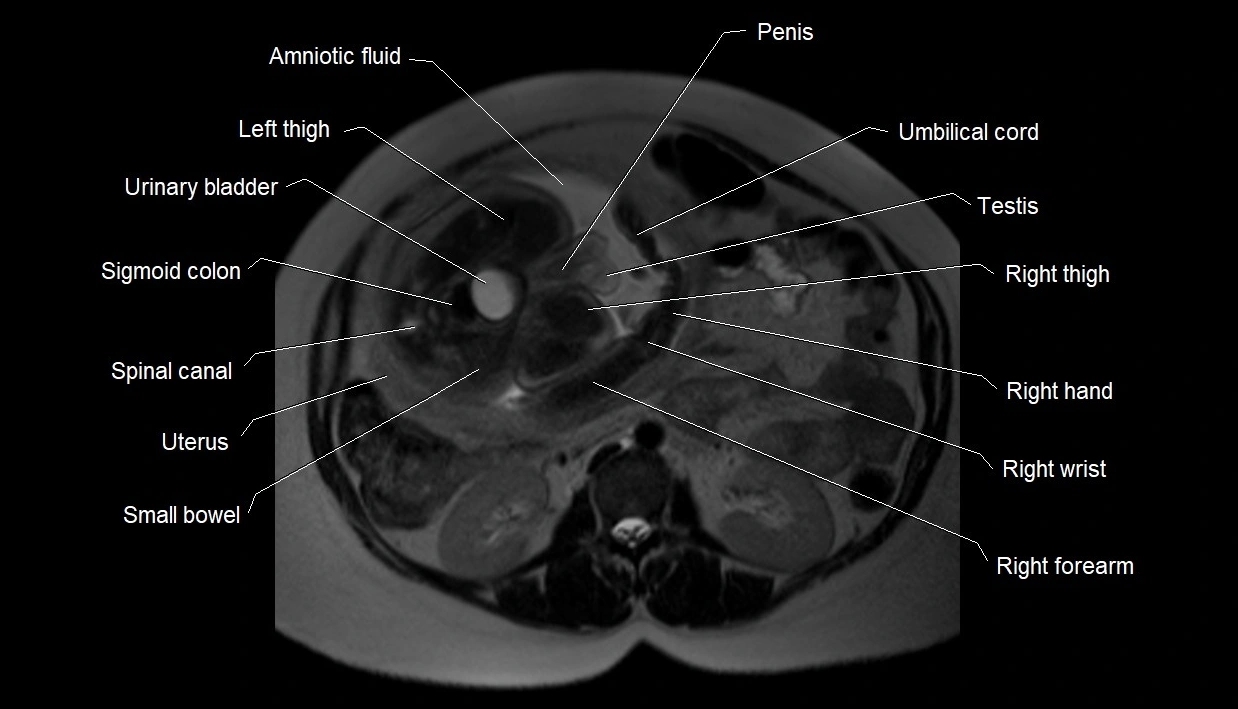

MRI Appearance

T1 GRE:

• Amniotic fluid shows low signal intensity (dark)

• Hemorrhage, infection, or proteinaceous content may cause focal or diffuse high signal intensity

MRI image

image